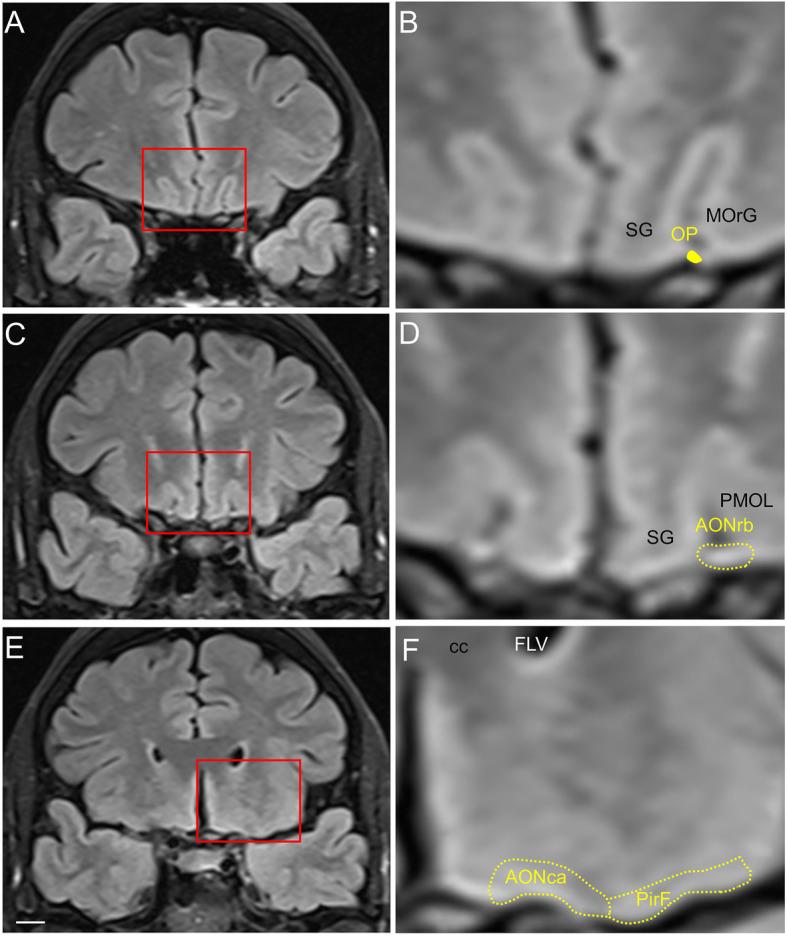

Alzheimer's and Parkinson's diseases are the most prevalent neurodegenerative disorders. Their etiologies are idiopathic, and treatments are symptomatic and orientated towards cognitive or motor deficits. Neuropathologically, both are proteinopathies with pathological aggregates (plaques of amyloid-β peptide and neurofibrillary tangles of tau protein in Alzheimer's disease, and Lewy bodies mostly composed of α-synuclein in Parkinson's disease). These deposits appear in the nervous system in a predictable and accumulative sequence with six neuropathological stages. Both disorders present a long prodromal period, characterized by preclinical signs including hyposmia. Interestingly, the olfactory system, particularly the anterior olfactory nucleus, is initially and preferentially affected by the pathology. Cerebral atrophy revealed by magnetic resonance imaging must be complemented by histological analyses to ascertain whether neuronal and/or glial loss or neuropil remodeling are responsible for volumetric changes. It has been proposed that these proteinopathies could act in a prion-like manner in which a misfolded protein would be able to force native proteins into pathogenic folding (seeding), which then propagates through neurons and glia (spreading). Existing data have been examined to establish why some neuronal populations are vulnerable while others are resistant to pathology and to what extent glia prevent and/or facilitate proteinopathy spreading. Connectomic approaches reveal a number of hubs in the olfactory system (anterior olfactory nucleus, olfactory entorhinal cortex and cortical amygdala) that are key interconnectors with the main hubs (the entorhinal-hippocampal-cortical and amygdala-dorsal motor vagal nucleus) of network dysfunction in Alzheimer's and Parkinson's diseases.